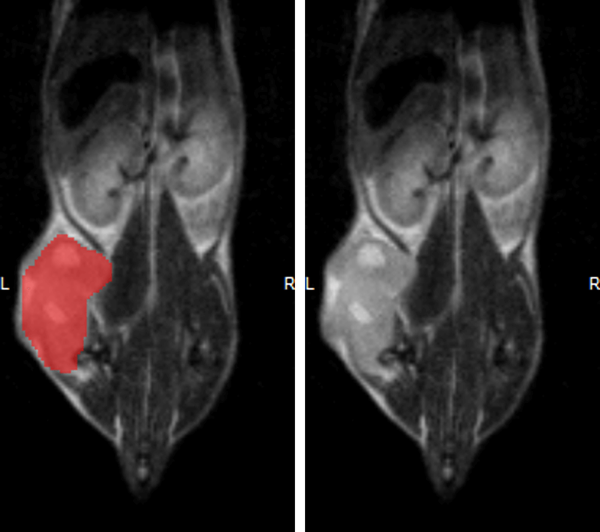

Monitoring the growth of xenograft tumor grown in the mouse hindlimb is identified with T2-weighted images. Segmentation of tumor region of interests (in red) on each tumor-containing slice allows accurate volume quantification. Image Credit: Scintica Instrumentation Inc

Hindlimb tumor growth: Monitoring the growth of xenograft tumor grown in the mouse hindlimb is identified with T2-weighted images. Segmentation of tumor region of interests (in red) on each tumor-containing slice allows accurate volume quantification. Image Credit: Scintica Instrumentation Inc